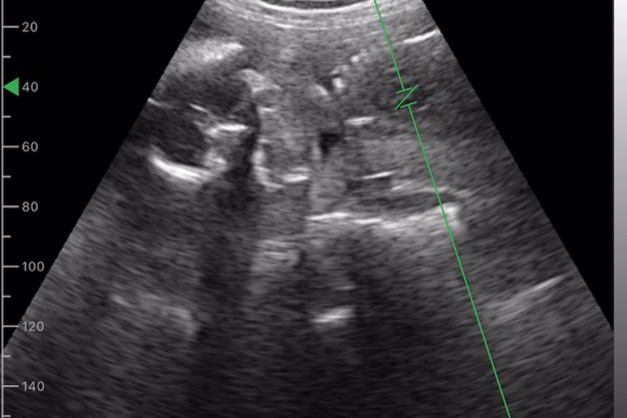

赤ちゃんが見える、心音も聞こえる

スマホで赤ちゃんが見れる安心感

ポケマムがあれば、ご自身のスマホでいつでもどこでも、お腹の中の赤ちゃんの様子をカンタンに見ることができます。

病院に行かなくても、気になったときにすぐ赤ちゃんの動きをチェックできるから、妊娠中の“安心感”をサポートします。